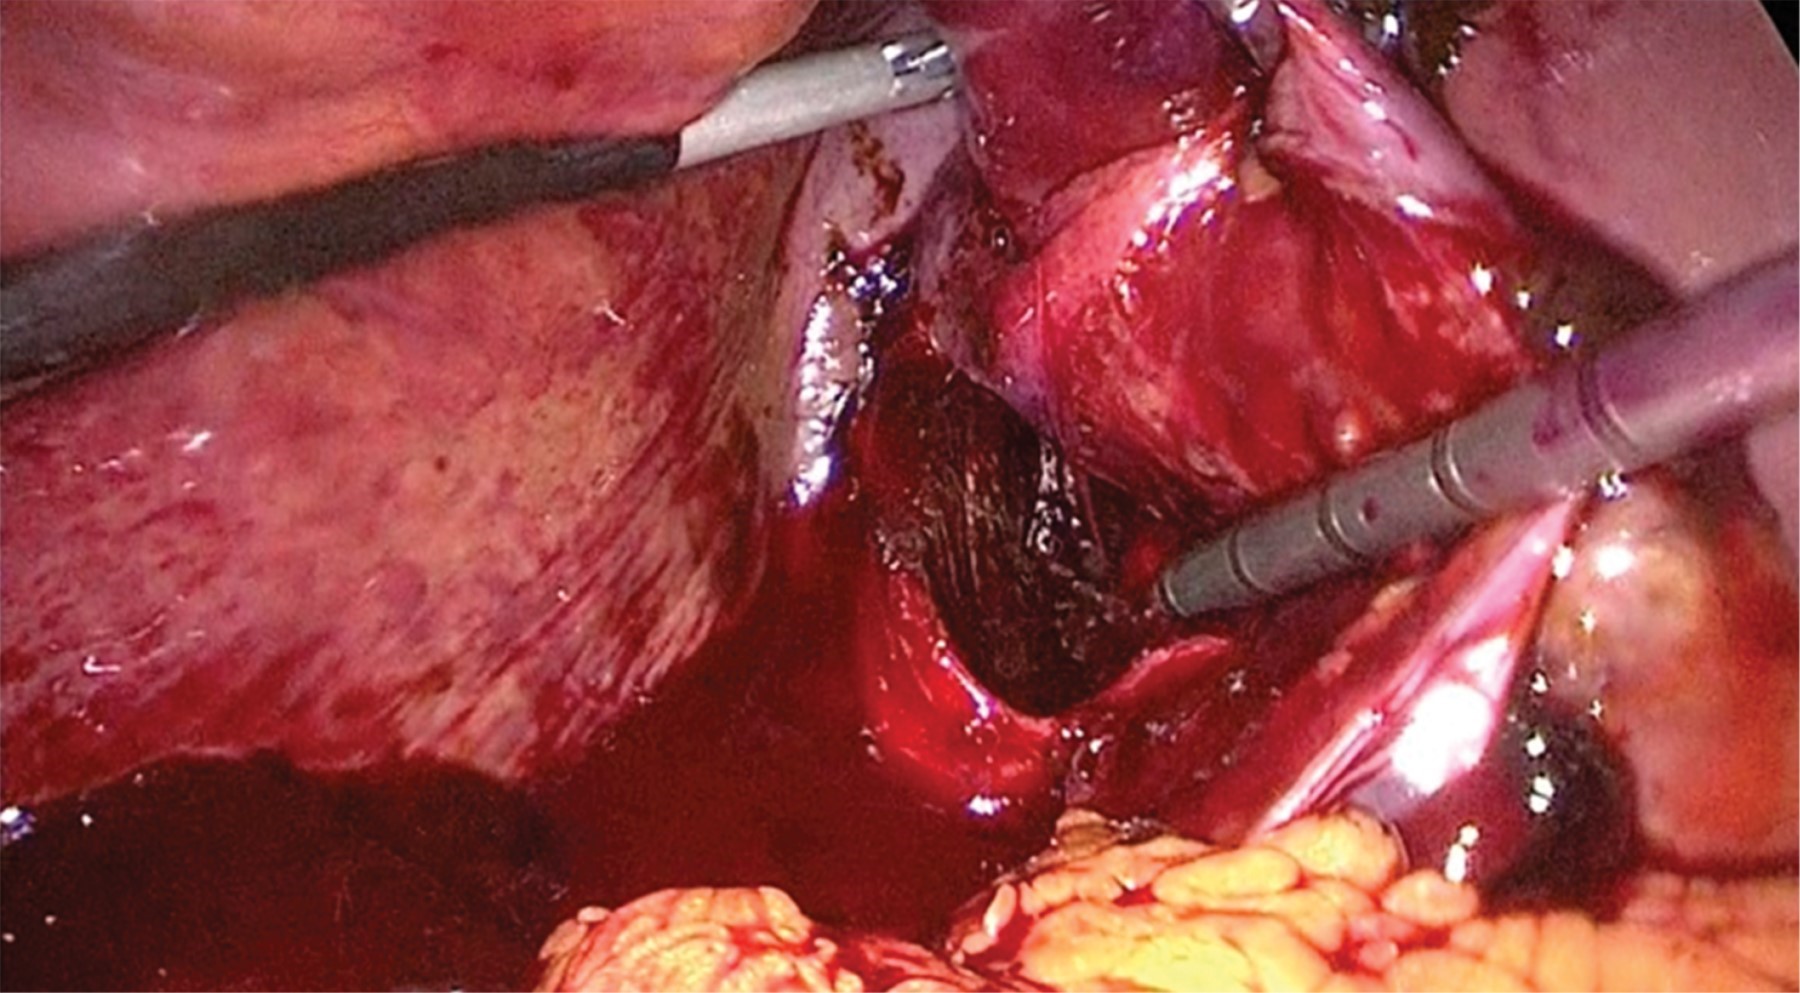

Bajo anestesia general, se colocó al paciente en posición americana; se realizó neumoperitoneo por puerto de 12 mm transumbilical con técnica abierta; se colocó, bajo visión directa, puerto de 10 mm subxifoideo y dos puertos de trabajo de 5 mm; se llevó a cabo laparoscopia diagnóstica que encontró vesícula biliar perforada, hemoperitoneo y sangrado activo intravesicular (Figura 3); se ejecutó aspirado de hemoperitoneo y bilis; se efectuó tracción cenital de vesícula biliar y disección de arteria cística; se practicó clipado con Hem-O-Lok® en arteria y conducto cístico, previa vista crítica (Figura 4); se resecó vesícula biliar con bisturí armónico; se retiró pieza quirúrgica utilizando bolsa endoscópica; se hizo lavado de cavidad y aspirado; se colocó Surgicel® en lecho quirúrgico y drenaje tipo Blake 19 Fr; se retiraron puertos de trabajo, bajo visión directa, sin evidencia de sangrado; se afrontó aponeurosis y piel; y se dio por concluido el acto quirúrgico; por último, se reportaron 1,000 ml de sangrado y un tiempo quirúrgico de 100 minutos. El paciente presentó buena evolución postquirúrgica, toleró la vía oral en el segundo día y se decidió su egreso en el quinto día postquirúrgico. Reporte de patología: vesícula biliar con colecistitis aguda perforada con necrosis transmural, no se observan datos de malignidad.

Figura 3